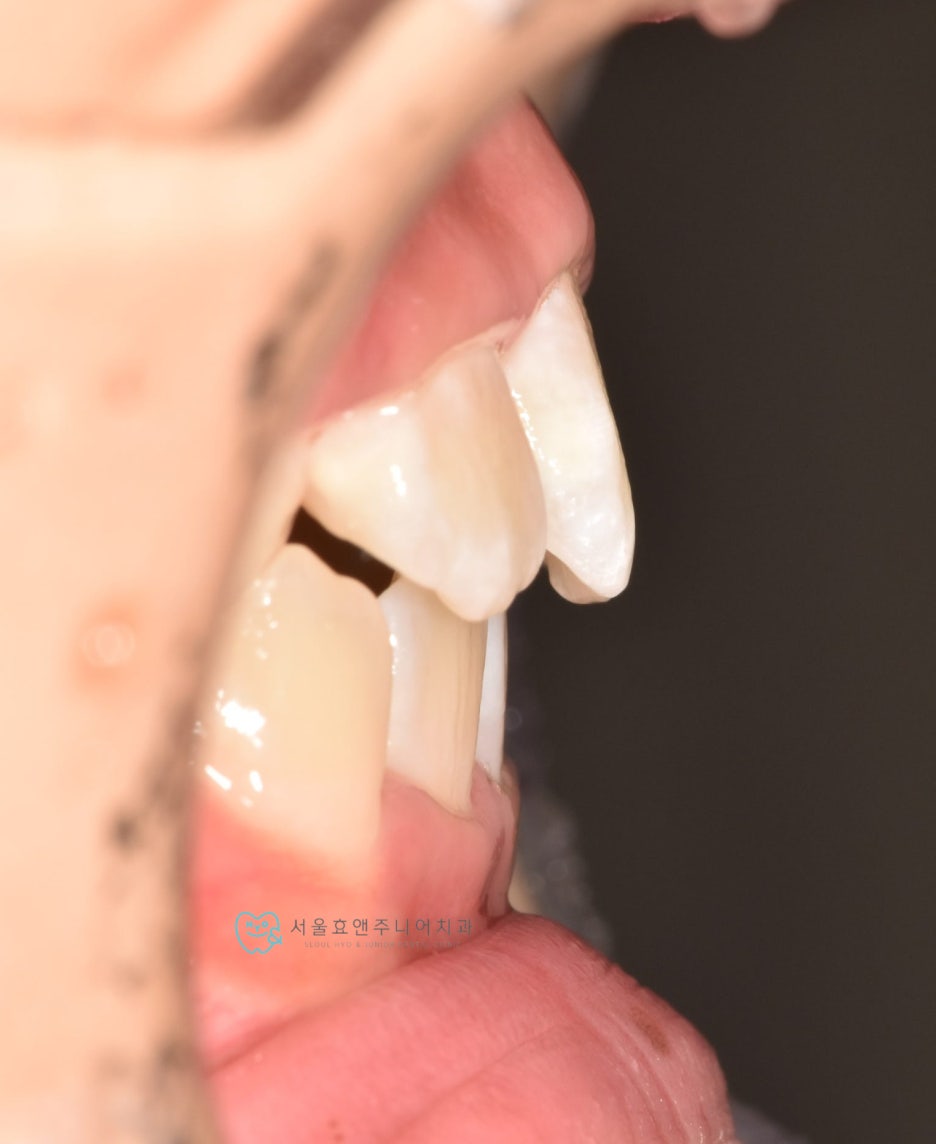

초진사진입니다

초진사진입니다. 11세 5개월 환아로, 반대교합을 보이고 있습니다. 반대교합으로 인해 치아가 부딪혀 치은퇴축(잇몸이 내려감)도 보이고 있네요.(화살표)